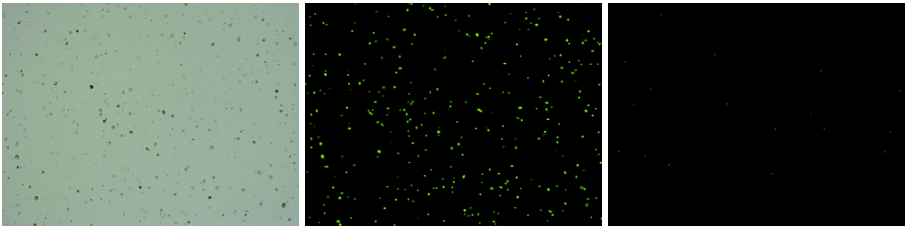

人腎組織樣品,細(xì)胞活率:97.86%,結(jié)團(tuán)率:8.68%

Tips:腎臟組織中細(xì)胞種類繁多且復(fù)雜,部分細(xì)胞類型解離過程中容易死亡,腎足細(xì)胞等粒徑比較大,建議采用單細(xì)胞核的方式,獲得的細(xì)胞類型更加全面。